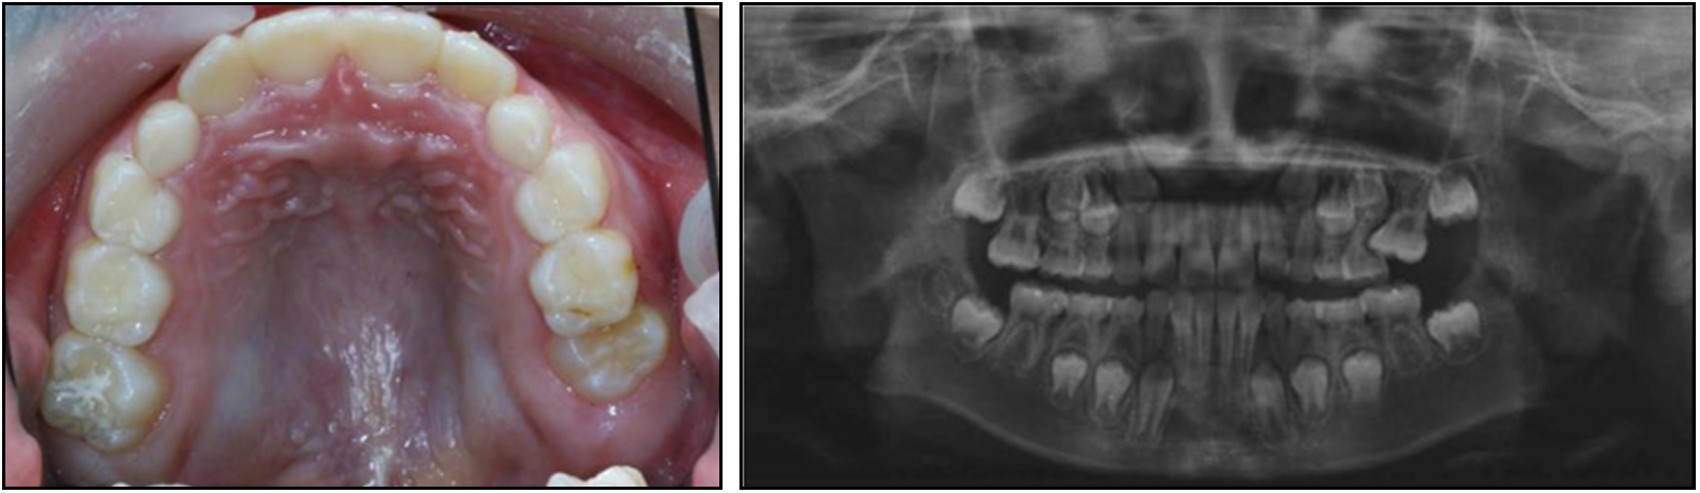

Ectopic eruption of the maxillary left first permanent molar, loss of the upper left second primary molar; Left, intraoral photograph; Right, Radiographic illustration